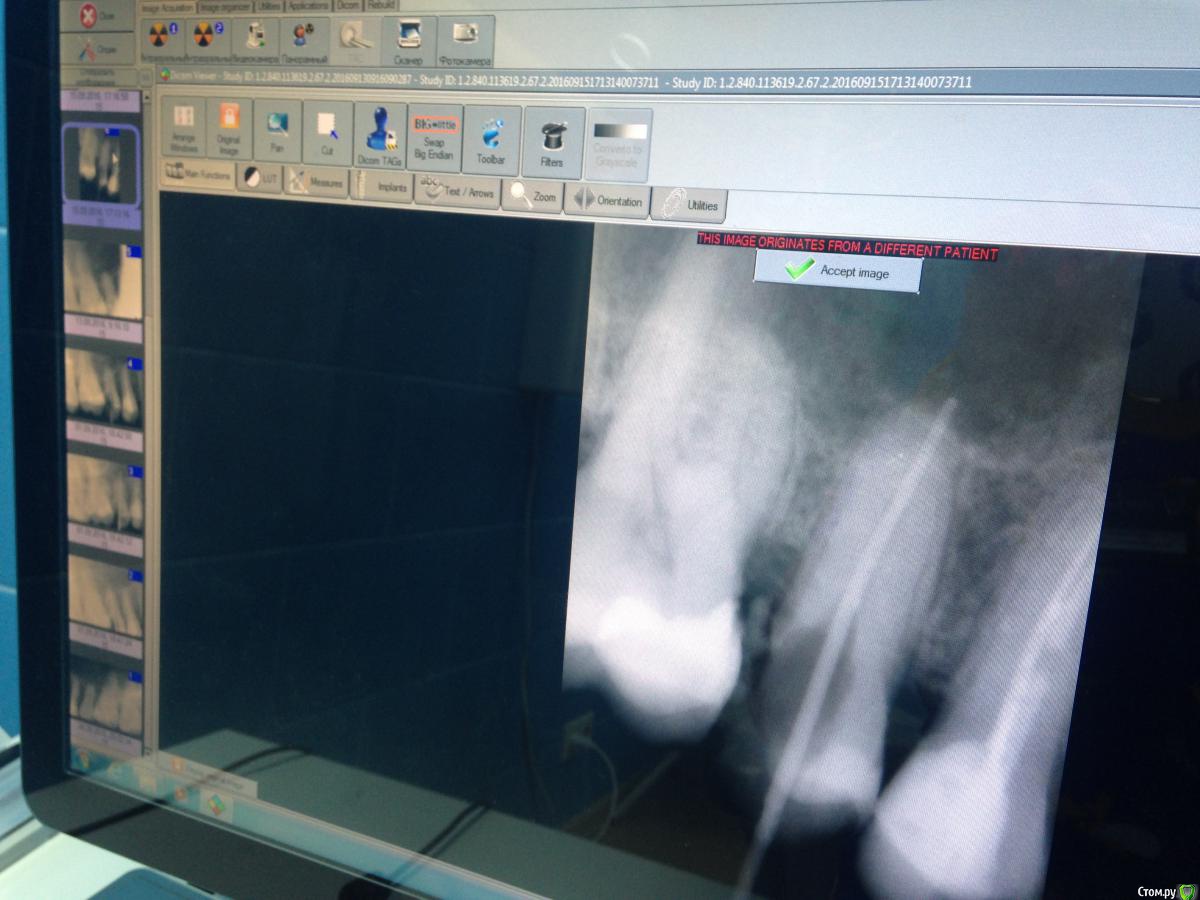

Malina11v Опубликовано 18 сентября, 2016 Поделиться Опубликовано 18 сентября, 2016 (изменено) Здравствуйте, хотела бы посоветоваться с коллегами. Такой случай: в начале июля приходила пациентка, ей другой доктор в нашей клинике поставила пломбы по глубокому кариесу на 15 и 16 зубы, через месяц она приходит еще к другой и говорит , что зуб болит уже месяц как, какой именно не знает, эта доктор принимает решение, что болит 15 и ставит депульпин. Через неделю пациентка приходит ко мне на обработку каналов, зуб Всю эту неделю ныл. В процессе обработки я расширяю канал до 40 и ставлю каласепт, Еще через неделю начинаю мыть парканом канал и пациенка указывает на резкую боль в области щеки и под глазом, понимаю что паркан зашел в пазуху, сразу начинаю мыть дистилированной водой обильно, ставлю крезофен и отправляю на неделю, так же пациенка указала на появление насморка, назначаю сосудосуживающие в нос и нимесил 5 дней, но гайморит у нее уже 10 лет как.Созваниваюсь с ней через пару дней , улучшения незначительные: зуб ноет, насморк есть, Назначаю сумамед 3 дня.через пару дней мою уже хлоргексином 2% и снова на каласепт. Через неделю: зуб эту неделю ныл, насморк немногл спал, но еще держится. Снова на каласепт и на две недели. Далее через две недели она приходит снова к другому врачу: зуб ноет , насморк есть, Приносит заключение ЛОРа с односторонним гайморитом , так же на снимках КТ определяется пломбировочный материал в пазухе и просвеь пазухи затемнен. Прилагаю снимки до лечения, во время обработки с инструментами и после пломбирования канала, На снимках с файлами в области верхушки видны белые тени, что это можеь быть? На кт их очень хорошо видно в виде полулунок, кроме каласепта и крезофена в каналах ничегл не было Изменено 18 сентября, 2016 пользователем Malina11v Ссылка на комментарий

Fibez Опубликовано 18 сентября, 2016 Поделиться Опубликовано 18 сентября, 2016 так может Вы нам КТ тогда и покажите? Раз их там хорошо видно? потому что тут кроме разбитой (резорбированной?) верхушки не видно ничего 1 Ссылка на комментарий

lightella Опубликовано 18 сентября, 2016 Поделиться Опубликовано 18 сентября, 2016 Каласепт - рентгеноконтрастный материал. Судя по тому, как разбит апекс, за верхушкой он и есть. 1 Ссылка на комментарий